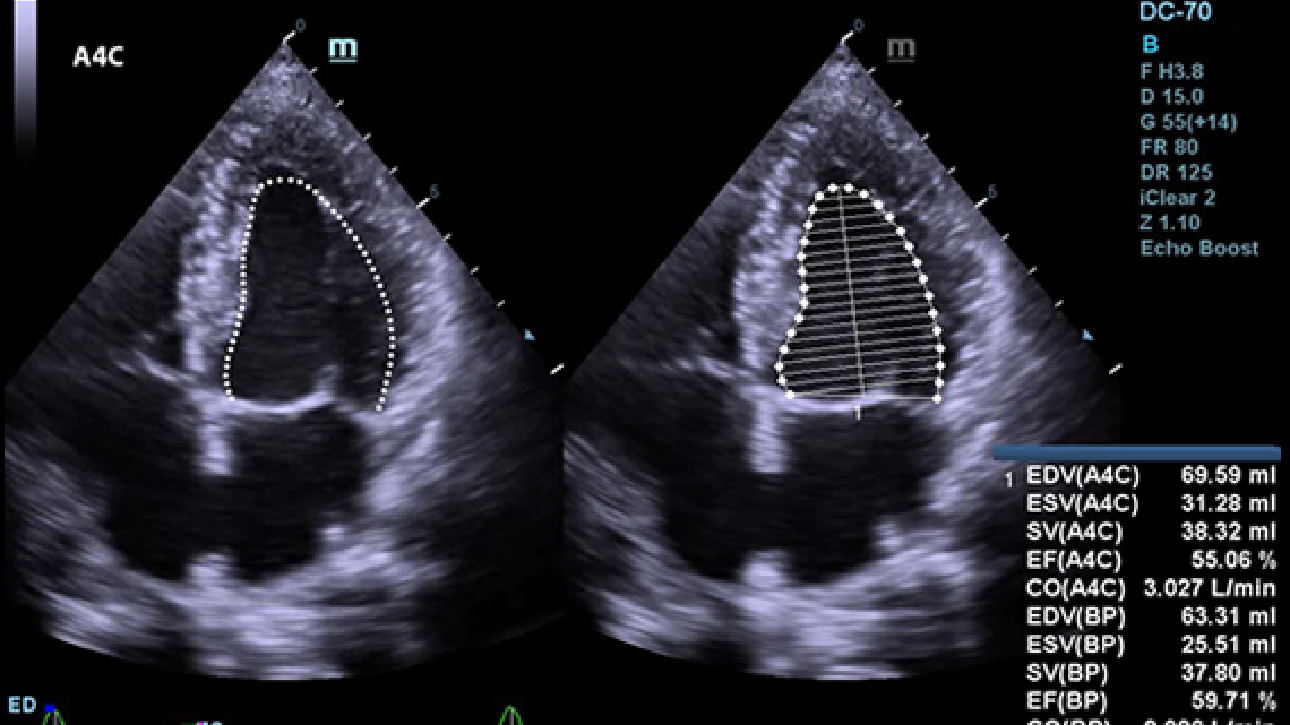

Echo Boost

MindrayŌĆÖs unique adaptive signal processing technology with intelligent echo detection, designed to utilize the native signal-to-noise information to enhance the weak echo signals while suppressing the surrounding clutter noise, providing more balanced image brightness and improved visualization of myocardium tissue layers.